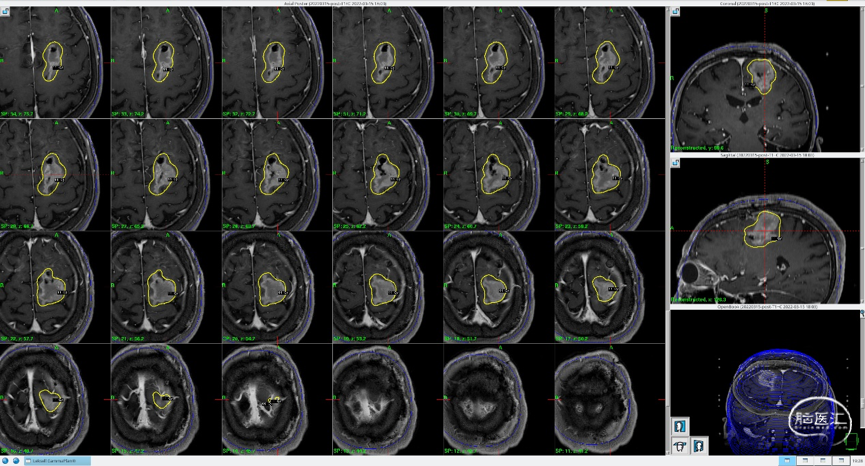

磁共振MRI定位扫描(T1增强序列,1mm轴位连续断层薄扫)。

磁共振MRI定位扫描(T2平扫,2mm轴位连续断层+T1增强序列,1mm轴位连续断层薄扫)。

制定立体定向伽玛刀治疗计划(术中薄扫核磁扫面共发现4个病灶,除术前的2个病灶外,还发现2个小病灶);

1)左额囊性病灶治疗计划(分期治疗):边缘剂量11Gy(55%,中心20Gy),照射体积:16.563cm3。

将患者摆位至伽玛刀机器上,进行照射。

总照射时长:75.6分钟